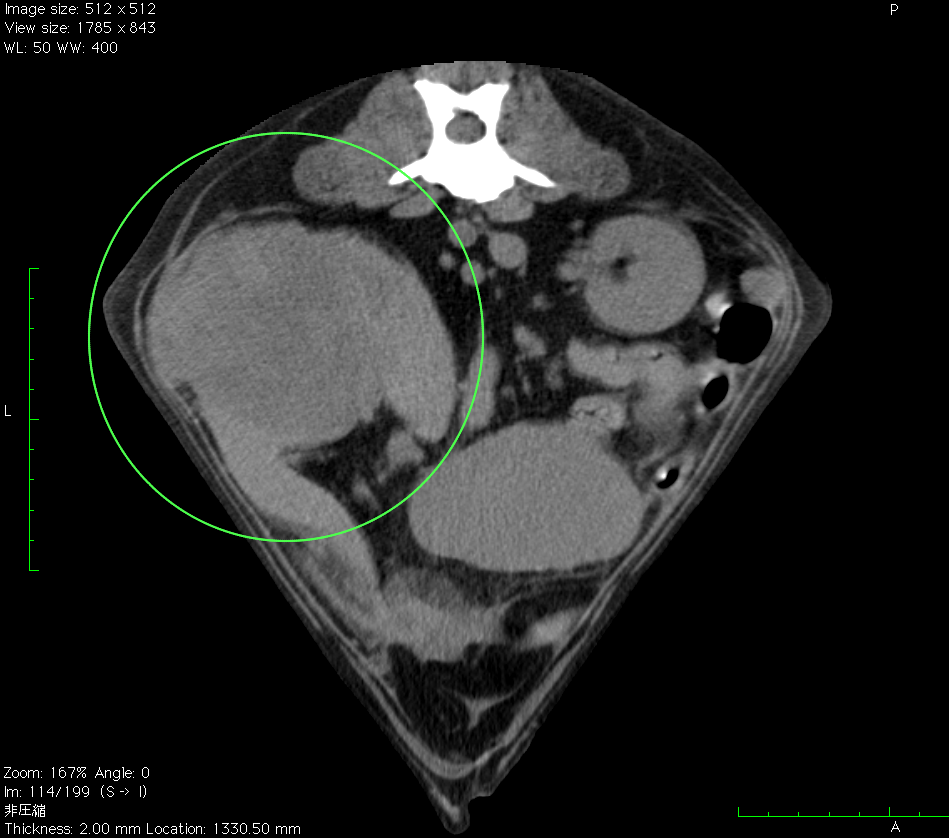

• 腹腔内病変

• 脾臓の血管肉腫

脾臓の血管肉腫